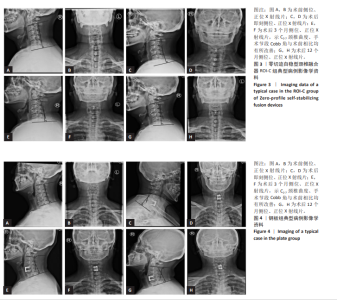

2.7 术后并发症评估 2.7.1 吞咽困难情况分析 在ROI-C组中,术后出现吞咽困难的病患数为4例,占该组总数的18%(4/22),此症状在术后3个月内自行缓解。相比之下,钢板组术后发生吞咽困难的患者较多,共计14例,发生率为34%(14/41);术后3个月时,钢板组内仍有7例(17%)患者持续存在吞咽困难;至术后6个月的随访时,这些患者的吞咽困难症状均得到显著改善或消失。统计结果显示,两组间在术后吞咽困难的发生率上未见显著性差异(χ2=1.788,P=0.181);ROI-C组术后3个月吞咽困难发生率显著低于钢板组(Fisher确切概率法P=0.041)。 2.7.2 邻近节段退变情况分析 ROI-C组与钢板组患者在术后3,6个月的时间点上,均未报告有邻近节段退变发生。术后12个月,ROI-C组中观察到邻近节段退变病例1例,占比5%(1/22);而钢板组内则出现3例邻近节段退变,占比7%(3/41),两组差异无显著性意义(χ2=0.029,P=0.866)。 两组术后12个月的上邻近节段和下邻近节段椎间隙高度均较术后即刻明显降低,但钢板组邻近椎间隙高度下降程度较ROI-C组明显增高,差异有显著性意义(P < 0.05)。两组间术前、术后即刻、术后3,6,12个月的C2-7 Cobb角、T1倾斜角、椎间隙高度相比差异均无显著性意义(P > 0.05)。 2.8 植入物与宿主的生物相容性 术后6个月时,ROI-C组出现1例未融合(5%),钢板组出现1例(2%);术后12个月时两组患者全部获得融合,两组间无明显差异(P < 0.05)。两组术后均未出现植入物周围感染、过敏反应、免疫反应及排斥反应。部分患者(ROI-C组3例、钢板组9例)术后出现体温轻度升高(小于38 ℃),在术后3 d内均得到恢复。术后各时间节点均未发现植入物破损、松动、脱落。 2.9 典型病例 影像学资料见图3,4。"